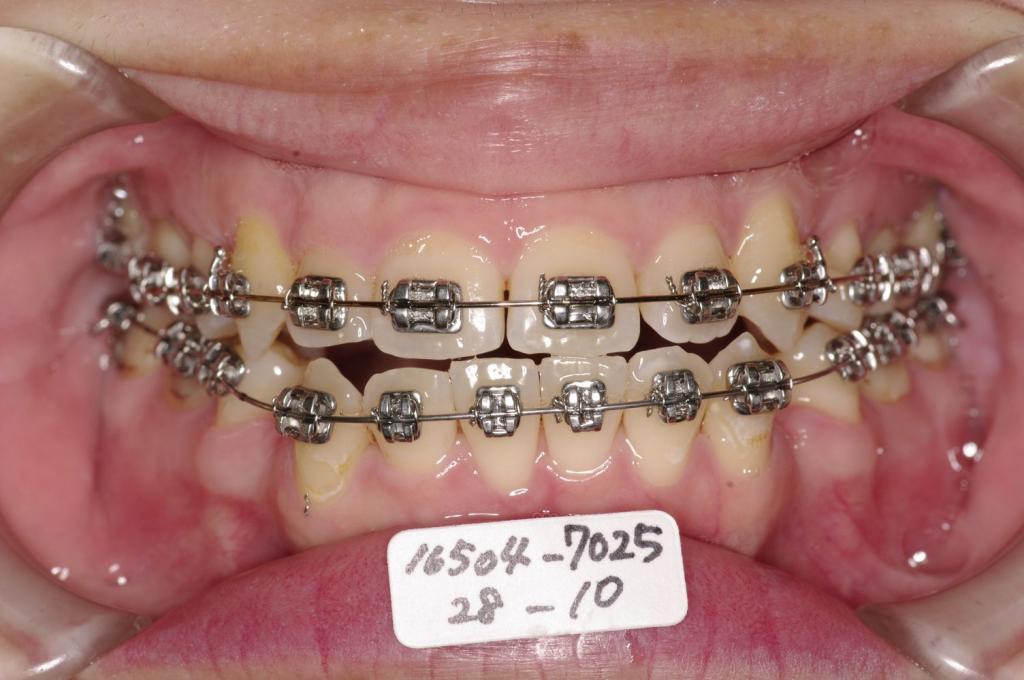

- 前歯、出っ歯・開咬の矯正治療

- 前歯の咬み合わせ